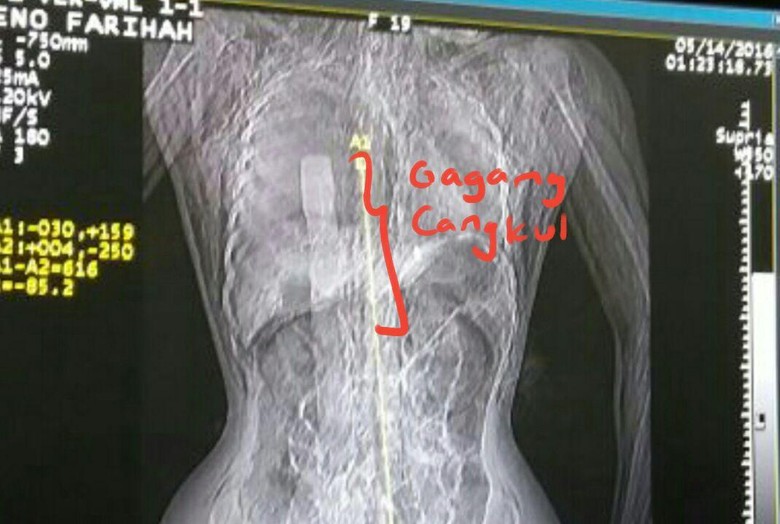

Eno, korban perkosaan sekaligus pembunuhan sadis oleh 3 remaja brandal di Tangerang ditemukan dalam kondisi memilukan. Sebuah pacul atau alat yang biasanya dibuat untuk bajak sawah tertancap di organ vitalnya hingga menembus jantung. Siapapun akan tak tega melihat kejadian yang menyayat hati ini. Namun siapa sangka ada manusia tolol yang tega menjadikannya bahan candaan.

Sebagai informasi Eno Farihah (18), seorang karyawan pabrik di Karawang diperkosa dan dibunuh oleh 3 remaja brandal ketika berada di mess pabriknya pertengahan Mei 2016. Ketiga pelaku nekat menghabisi eno karena cinta yang bertepuk sebelah tangan. Dan ketika ditemukan kondisi Eno sangat memilukan dan menyayat rasa kemanusiaan tersebut. Kasus ini masih dalam penanganan pengadilan untuk memberikan hukuman yang setimpal atas aksi sadisnya ini.